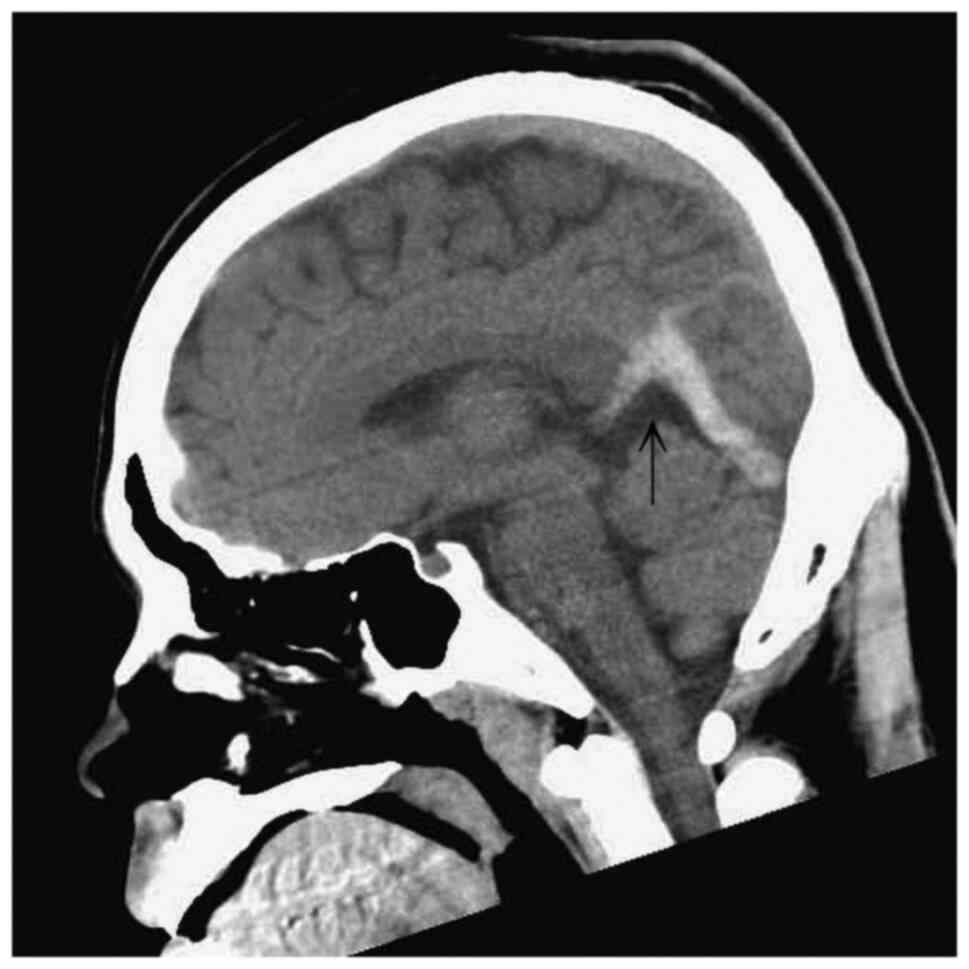

Figure 2

Lateral view of the computed tomography scan of the head illustrating an abnormal hyperattenuation (arrow) in the straight sinus and bilateral transverse sinuses.

A computed tomography (CT) scan of the head revealed an abnormal hyperattenuation in the straight sinus and bilateral transverse sinuses (Figs. 1 and 2). A diagnosis of CSVT was made following a consultation with a neurologist. The patient was treated with enoxaparin at 6,000 IU, levetiracetam at 1,000 mg and mannitol at 100 ml via an intravenous drip. Following admission, a magnetic resonance venography revealed the absence of flow in the straight sinus and bilateral transverse sinuses (Fig. 3). A thrombophilic investigation revealed a plasma homocysteine level of 59.03 µmol/l (upper normal limit, 15.39 µmol/l) and a vitamin B12 level of <148 (lower normal limit, 187 pg/ml). The levels of protein C (70-140%), protein S (60-130%) and antithrombin III (75-125%) were within the normal range. CSVT secondary to homocystinemia was diagnosed, which is an unusual, yet treatable condition.